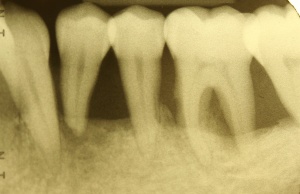

Diagnostische Parameter für die Beurteilung der dentalen und der periimplantären Zustände sind die Plaqueakkumulation, die Sondierungstiefen des Zahnes und des Implantates, Bluten auf Sondierung, Suppuration und der radiographische Knochenverlust (Salvi & Lang 2004). Unabdingbar ist im Minimum eine Sechspunktmessung (Sondiertiefen und klinischer Attachmentlevel). Immer wieder hört man von der Befürchtung, dass durch ein Sondieren des Implantates dieses geschädigt wird. In einer histomorphometrischen Studie an Hunden haben Etter et al. (2002) die Heilung des periimplantären Weichgewebes nach standardisiert klinischem Sondieren untersucht. Die Heilung des Epithelansatzes nach Sondierung des gesunden periimplantären Gewebes ist nach fünf Tagen abgeschlossen. Erfahrungsgemäß ist bei besonders aufmerksamem und vorsichtigem Sondieren ein äußerst geringes Verletzungsrisiko gegeben. Auch diese Techniken können in einem Praktikum bei einem Parodontologen aufgefrischt werden.

Im Rahmen einer solchen Nachuntersuchung werden neben der Plaqueakkumulation die klinischen Parameter Sondiertiefe und klinischer Attachmentlevel (6-fach je Zahn / Implantat), Bluten nach Sondieren (BnS), Suppuration und gegebenenfalls der radiographische Knochenverlust (Salvi & Lang 2004) erfasst.